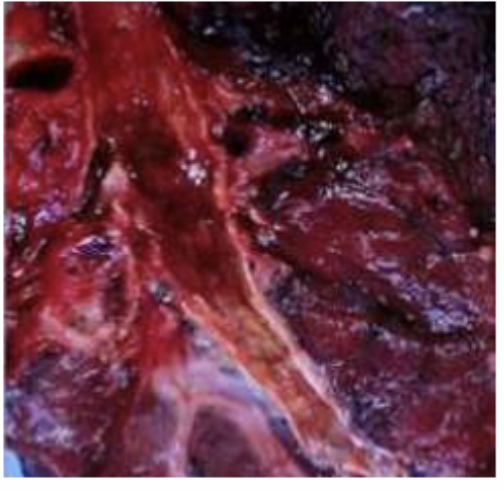

Bronquiectasias